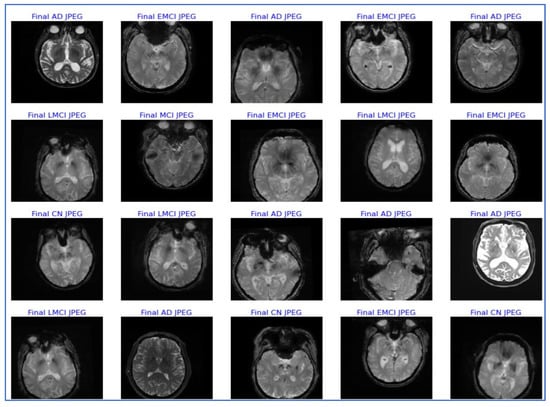

| Class | Training Data | Validation Data | Testing Data | Total |

|---|---|---|---|---|

| CN | 400 | 90 | 90 | 580 |

| MCI | 400 | 90 | 90 | 580 |

| EMCI | 400 | 90 | 90 | 580 |

| LMCI | 400 | 90 | 90 | 580 |

| AD | 400 | 90 | 90 | 580 |

| TOTAL | 2000 | 450 | 450 | 2900 |

| Metrics | Precision | Recall | F1-Score | Support |

| Final AD JPEG | 0.98 | 0.98 | 0.98 | 90 |

| Final CN JPEG | 0.95 | 0.90 | 0.93 | 90 |

| Final EMCI JPEG | 0.96 | 0.96 | 0.96 | 90 |

| Final LMCI JPEG | 1.00 | 1.00 | 1.00 | 90 |

| Final MCI JPEG | 0.93 | 0.98 | 0.95 | 90 |

| Accuracy | 0.96 | 450 | ||

| Macro Avg. | 0.96 | 0.96 | 0.96 | 450 |

| Weighted Avg. | 0.96 | 0.96 | 0.96 | 450 |